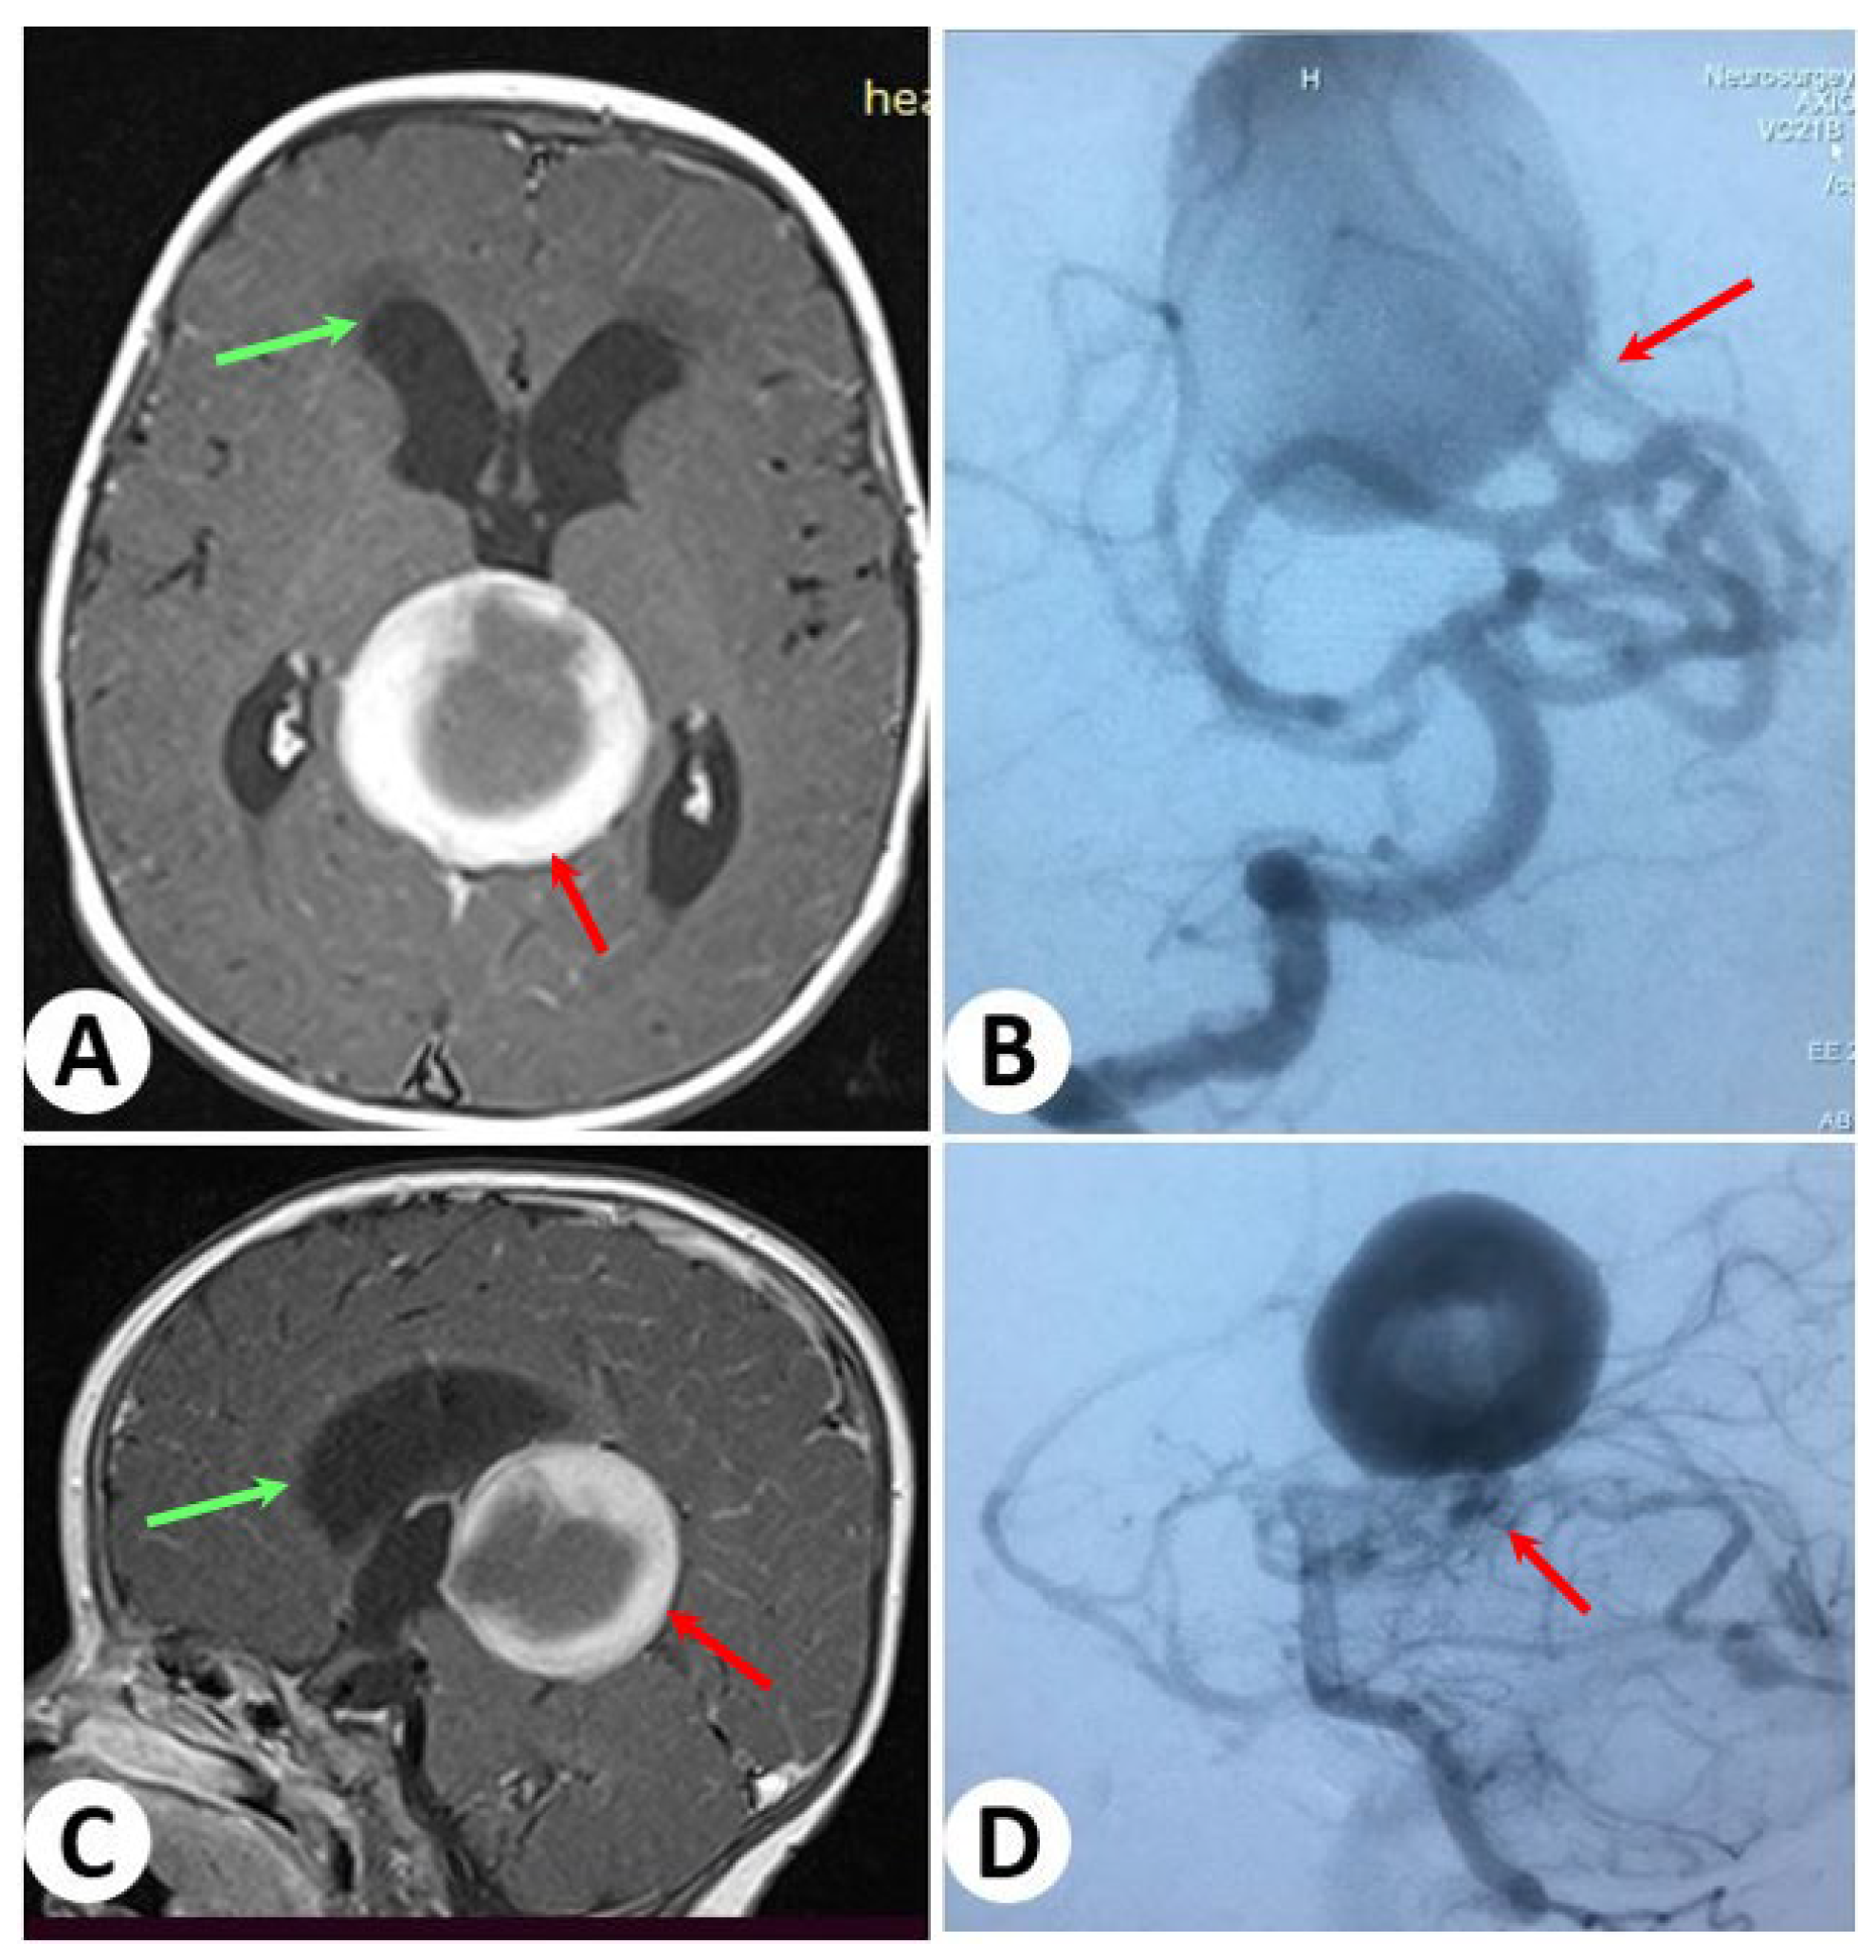

3.1. Illustrative Cases: Case 1

3.2. Illustrative Cases: Case 2